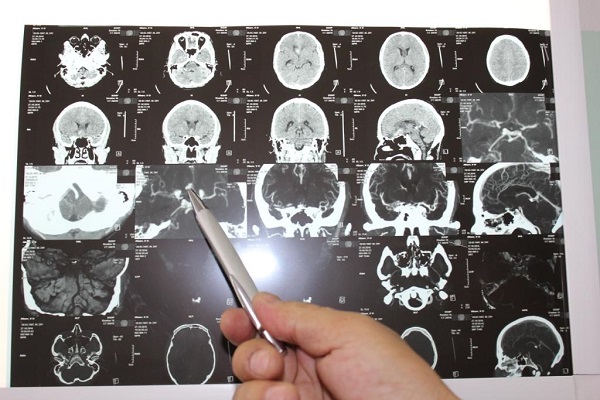

В республиканской больнице имени Семашко провели сложную операцию 29-летнему жителю Улан-Удэ, который находился на грани жизни и смерти. Ему сделали эндоваскулярную эмболизацию мешотчатой аневризмы передней мозговой артерии.

Пациент поступил в отделение реанимации имени Семашко из инфекционной больницы, где находился с подозрением на менингит. Мужчина находился в тяжелейшем состоянии. Операция была проведена сразу же в день поступления.

- У пациента произошло субарахноидальное кровоизлияние с прорывом крови в желудочки мозга. В связи с врождённой слабостью синусового узла трепанация черепа была противопоказана. Поэтому операция была проведена эндоваскулярным методом, - сообщает пресс-служба республиканской больницы.

В этот момент специалисты больницы каждую секунду следили за состоянием пациента, в буквальном смысле держали руку на пульсе. Операционная бригада в составе хирурга Игоря Бухаева, ассистента Андрея Борхонова, анестезиолога Юрия Жигжитова и операционной сестры Айталины Старостиной в течение 45 минут боролась за жизнь молодого пациента. Во время операции мешотчатая аневризма ПМА-ПСА выключена из кровообращения.

В этот момент специалисты больницы каждую секунду следили за состоянием пациента, в буквальном смысле держали руку на пульсе. Операционная бригада в составе хирурга Игоря Бухаева, ассистента Андрея Борхонова, анестезиолога Юрия Жигжитова и операционной сестры Айталины Старостиной в течение 45 минут боролась за жизнь молодого пациента. Во время операции мешотчатая аневризма ПМА-ПСА выключена из кровообращения.

- После субарахноидального кровоизлияния очень высок риск повторного разрыва аневризмы с возможным летальным исходом. Наша главная задача – предотвратить этот повторный разрыв. Мы вводим спираль в полость аневризмы и пломбируем его изнутри, выключая аневризму из кровотока, - говорит врач-нейрохирург Игорь Бухаев.